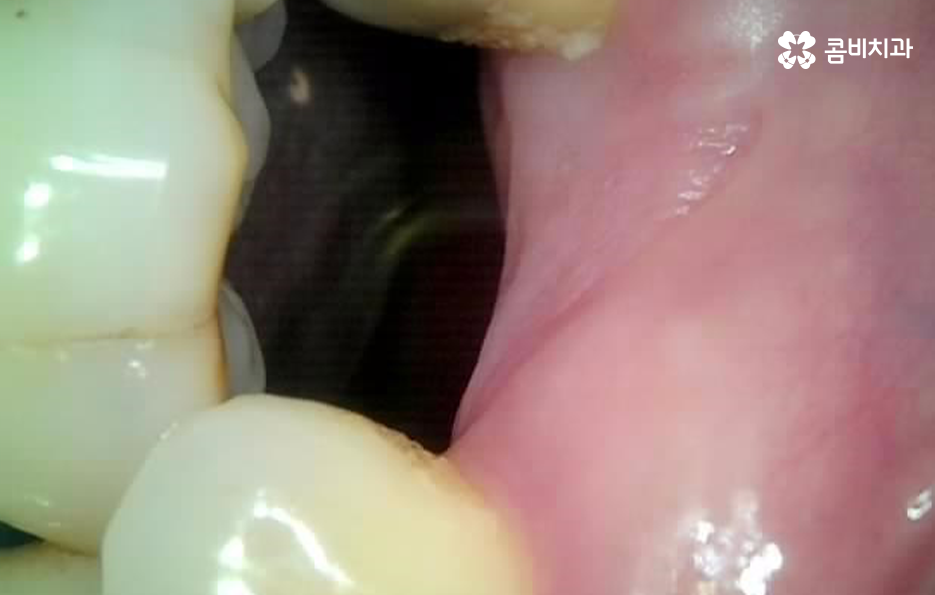

치아 옆면 충치의 경우 사실 더 큰 문제가 될 수 있는 점은 발견 자체가 늦어지는 경우가 많고 눈에도 잘 띄지 않기 때문에 환자분께서 검진을 미루고 다소 시리거나 아파도 참고 지내다 보면 치아의 옆부분에서 충치가 시작되었기 때문에 치아의 신경조직까지 손상되기에 쉬운 위치라는 점에서도 신경치료로 이어지는 경우도 흔하게 발생되고 있어요

우선 치아로 따지자면 치아의 씹는 면에 발생된 충치는 치료도 비교적 쉬운 편이고 치아의 구조로 볼 때도 치아의 윗 부분은 법랑질이 신경과의 거리가 어느정도 있기 때문에 충치가 몇번 치료해도 레진이나 인레이 정도로 치료가 끝낼 수 있는 경우가 많은데 치아 옆면 충치의 경우에는 치아 사이에 하루 이틀 음식물이나 이물질이 낀 것이 아니라 오랜 시간 동안 지속적으로 치실 사용이나 스케일링을 잘 안한 경우에 주로 발생되기 때문에 단순히 어금니 혹은 사랑니 주변에만 발생되는 것이 아니라 치아의 여러 부분에서 치아 옆면 충치가 동시에 발생되는 경우가 있는데요

치아 옆면 충치는 치아와 치아 사이에 맞닿는 부분에 발생하기 때문에 최소 2개의 치아에서 발생되는 경우가 일반적이며 습관적인 부분이 원인이 되기 때문에 치과 치료가 늦어지면 여러 치아에서 동시에 발생되는 경우도 자주 볼 수 있기 때문에 치아 수명을 급격히 저하시키는 원인이 되고 있어요